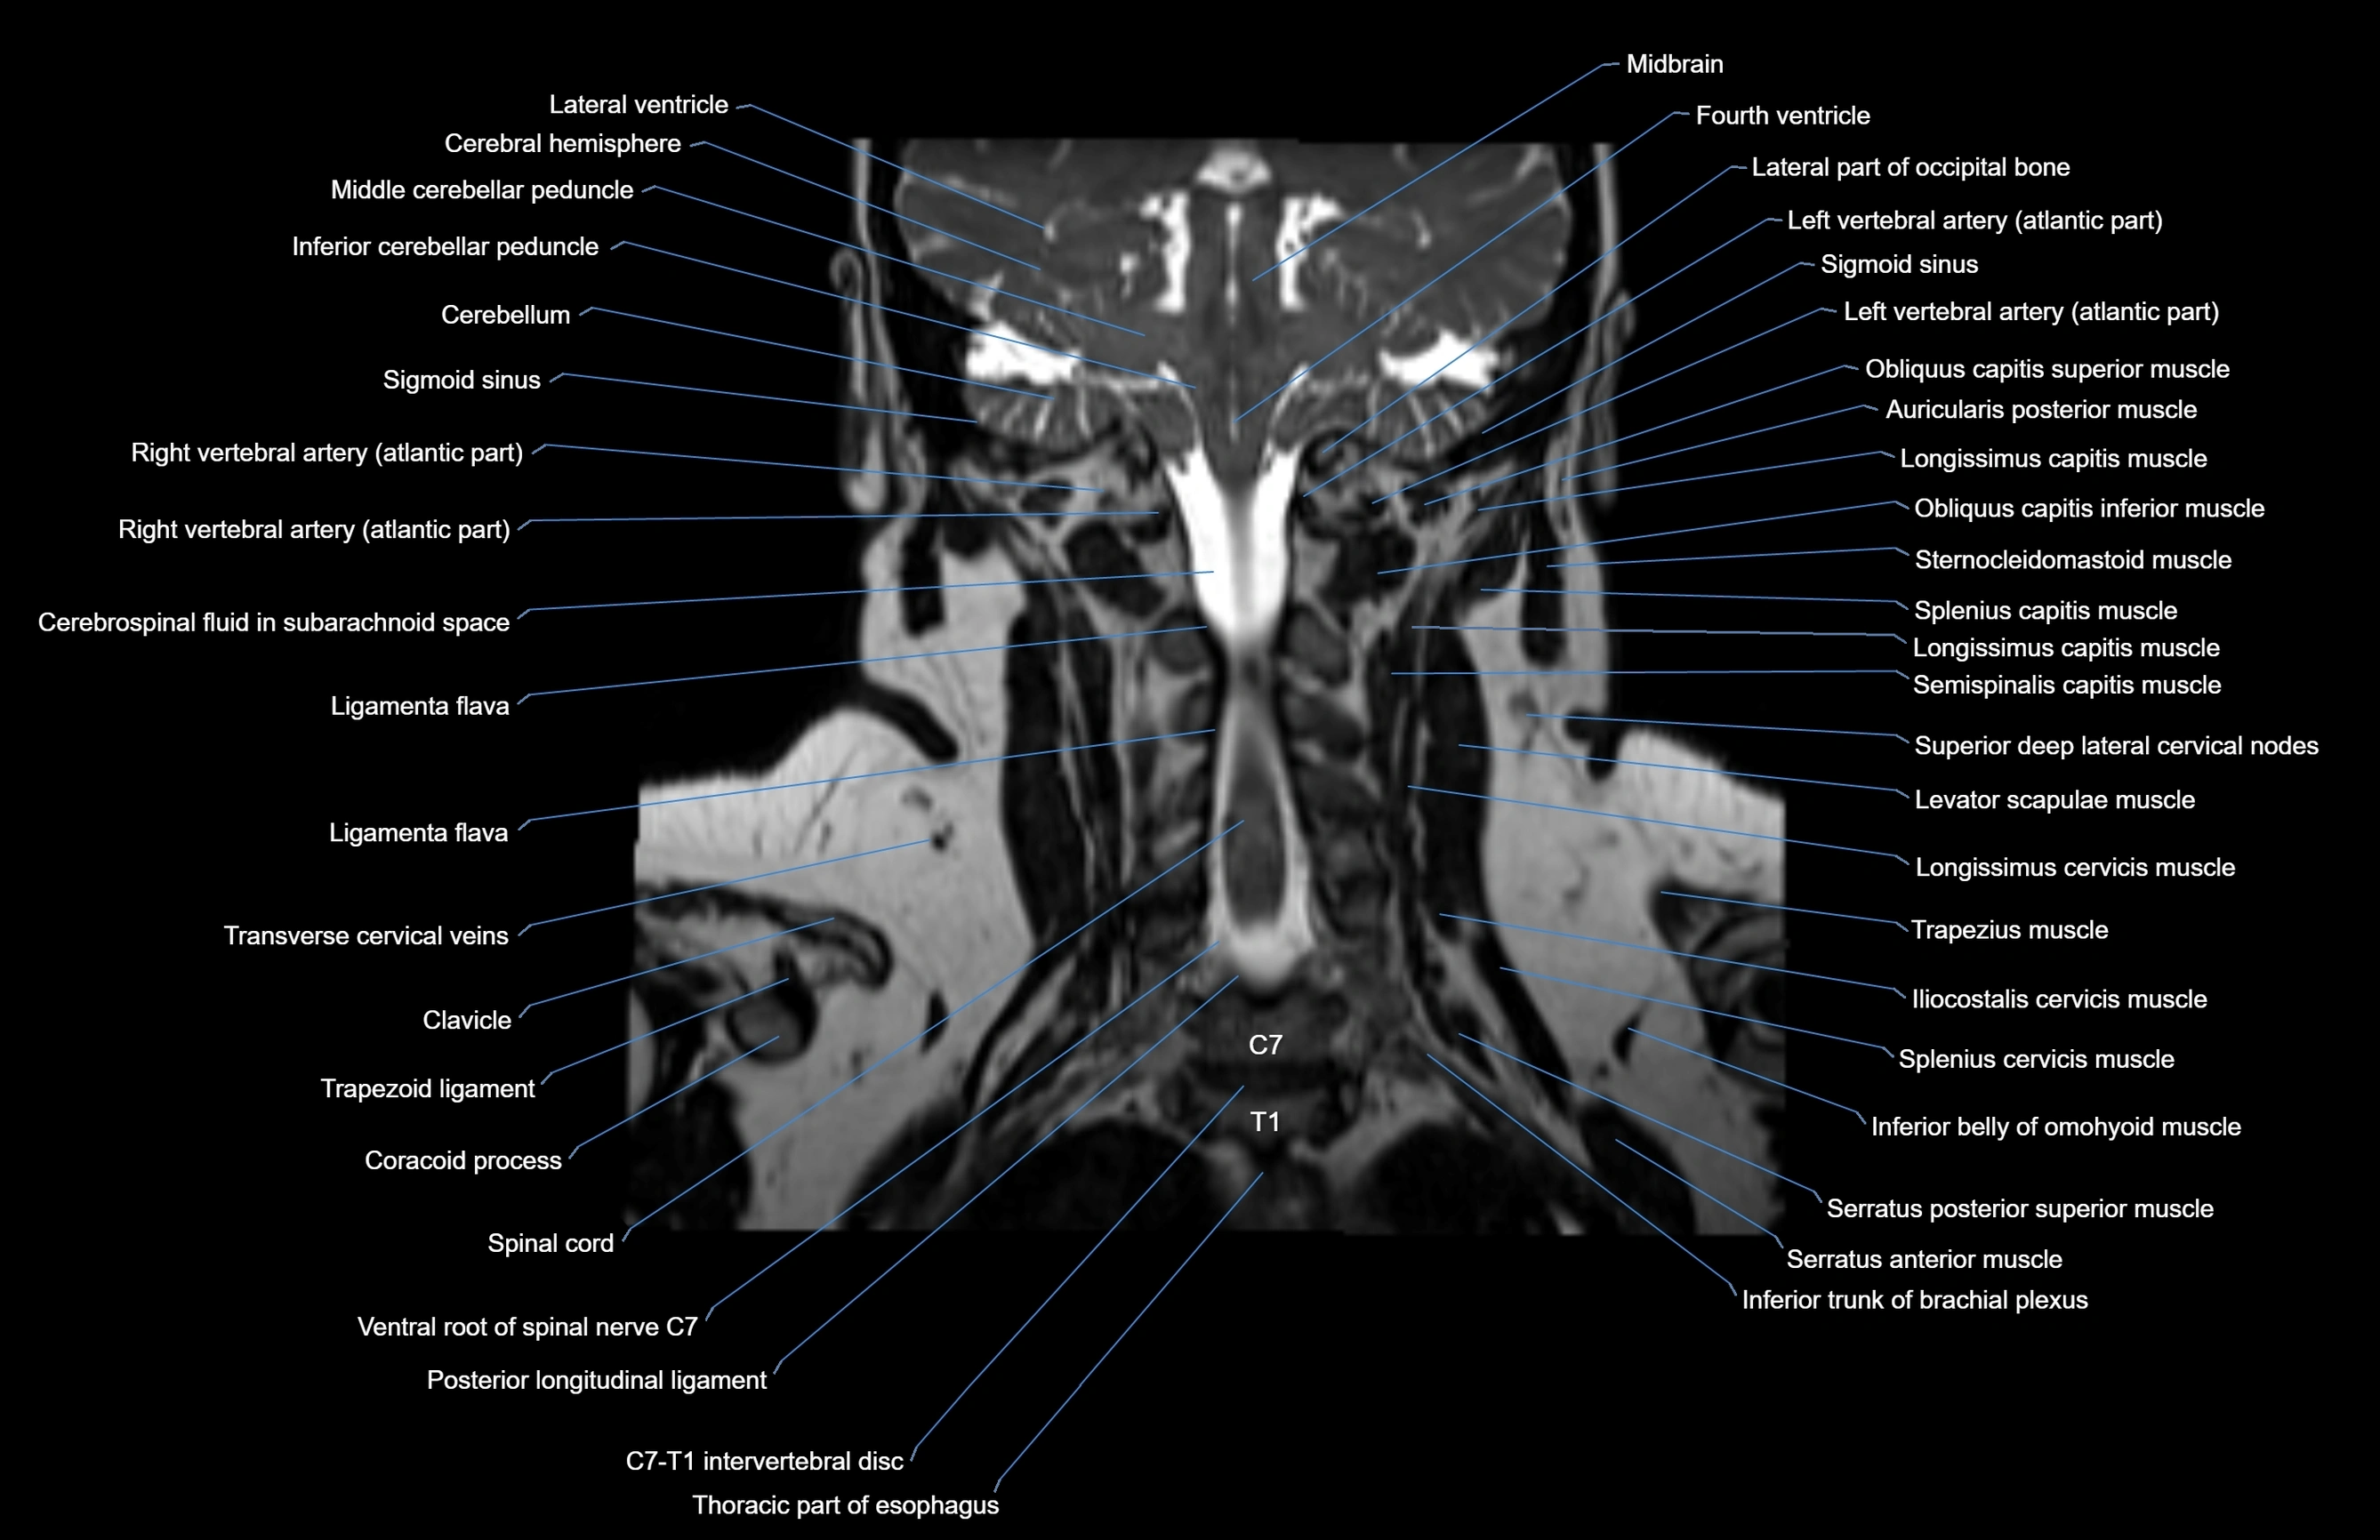

- Cerebellum

- Inferior cerebellar peduncle

- Left vertebral artery (atlantic part)

- Ligamenta flava (Ligamentum flavum)

- Longissimus cervicis muscle

- Middle cerebellar peduncle

- Right vertebral artery (atlantic part)

- Spinal cord

- Thoracic part of esophagus

- Trapezius muscle